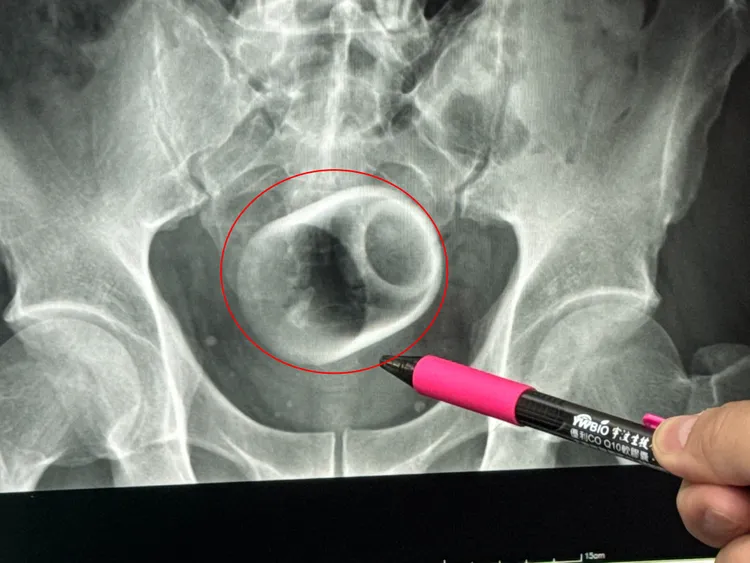

一名男子把陶瓷杯塞進肛門,X光片顯示杯子位於骨盆腔內。李綜合提供

駐診在李綜合醫院的台中榮總外科醫師吳坤達表示,該名患者到院時,自訴3天無法大便非常困擾,害羞不敢提及自己肛門塞了一個杯子,經過X光攝影,看到骨盆腔內有一個杯子,杯口朝下,因此,馬上安排進手術室,要把杯子拿出來。